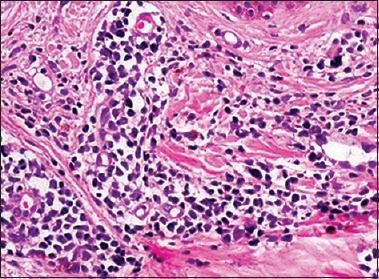

SkIndia Quiz 18: Multiple erythematous nodules in a 30-year-old woman.